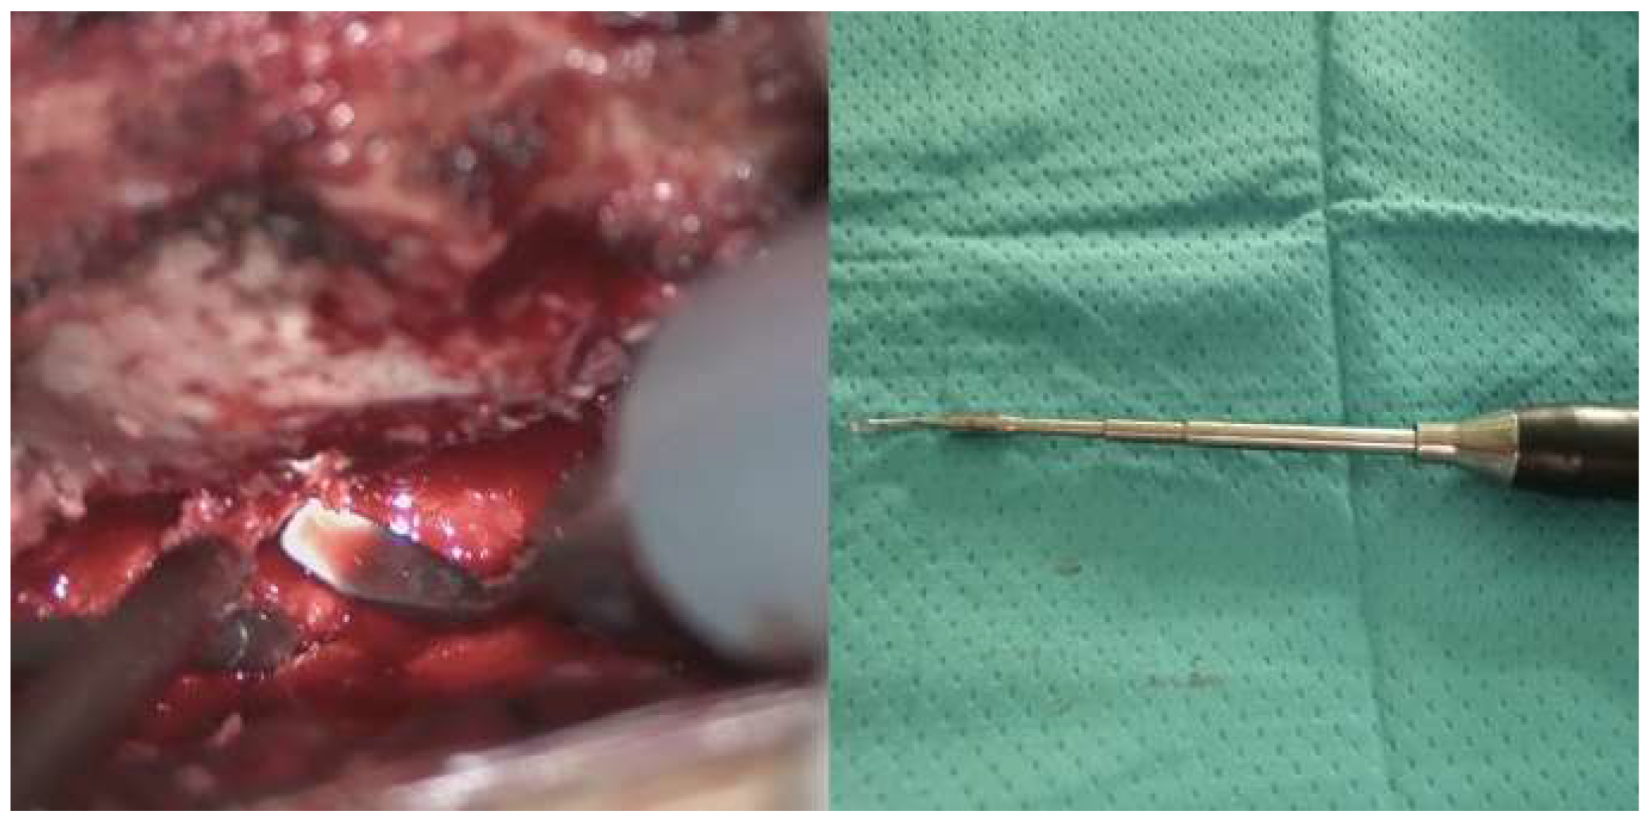

The patient underwent a laminotomy and microsurgical resection of the lesion. Intraoperatively, a vascular malformation resembling a dural arteriovenous fistula (SDAVF) was observed and sealed using bipolar cautery and scissor separation [Figure 2]. Histopathological examination confirmed the diagnosis of hemangioma, with immunohistochemical staining positive for ERG and CD34.

The patient was positioned prone, and a midline incision was performed, followed by bilateral muscle dissection and laminotomy at D11-D12 using a Piezoelectric osteotome (Mectron s.p.a – Italy) [Figure 4]. Under the operating microscope, a dural opening was made, exposing the lesion, which appeared as an exophytic protrusion from the surface of the left posterior spinal cord, surrounded by a vascular malformation with multiple arteriovenous fistulas on the pial surface [Figure 2]. Coagulation and disconnection of the fistulas were performed first. An incision was made around the lesion, which exhibited a firm consistency. Due to the inability to remove the pathological tissue without traction, an ultrasonic aspirator was used for resection. Meticulous hemostasis was achieved. The dura mater was sutured, and the laminae were repositioned using plates and screws. Standard wound closure was performed.

Figure 2. Intraoperative findings. Upper left: Visualization of the hemangioma (red arrow) associated to the vascular malformation resembling a dural arteriovenous fistula (yellow arrow). Upper right: Sealing of the fistula using bipolar cautery. Bottom left: Macroscopic color change following fistula closure. Bottom right: Macroscopic appearance following hemangioma removal. .